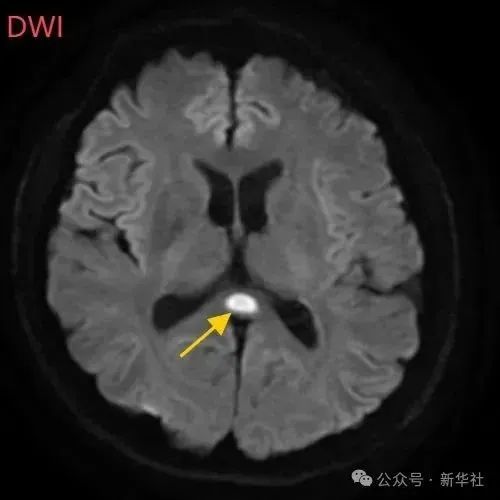

医生摇摇头,经过头部磁共振平扫、弥散、增强影像等检查,医生诊断,小董是得了一种比较少见的病症:可逆性胼胝体压部综合征。

小董的影像结果显示,胼胝体压部发生病变